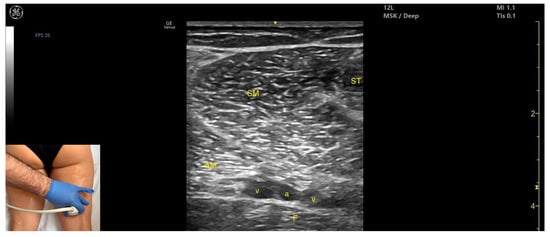

3.3. Psoas Major

3.3.1. Overview

3.3.2. Ultrasound Identification

3.3.3. Key Ultrasound Landmarks

- Muscle position: It is the deepest muscle mass at this level.

- External fascia: It presents a pronounced fascia that separates it from the erector spinae and quadratus lumborum, aiding in safe botulinum toxin injection.

- Dynamic evaluation: During dynamic evaluation, when scanning proximo-medially toward the costal arch, its origin is visualized from the T12 to L5 vertebrae.

- Contraction is visible during hip flexion, as well as lumbar spine flexion and lateral inflection maneuvers.

- The psoas major can also be visualized using a longitudinal transducer position, placed superior to the iliac crest and 2 cm lateral to the L4 spinous process. In this view, both the psoas major and the overlying quadratus lumborum are seen superficial to the intraperitoneal space.

3.3.4. Clinical Implications and Injection Strategy